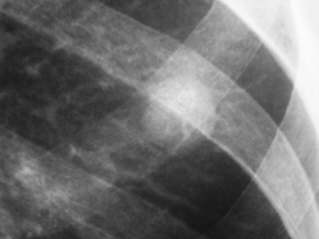

Иллюстрация 4. На рентгенограмме органов грудной полости, произведенной в прямой стандартной проекции, дифференцируется некоторая неровность и нечеткость контуров описанной тени.

Иллюстрации 5, 6. Фрагменты рентгенограммы «с увеличением изображения». Фиксируется некоторая нечёткость контура. По медиальному контуру дифференцируется «вырезка Риглера». По латеральному контуру определяется «тяжистость» к костальной плевре.

Иллюстрация 7. Фрагмент рентгенограммы.